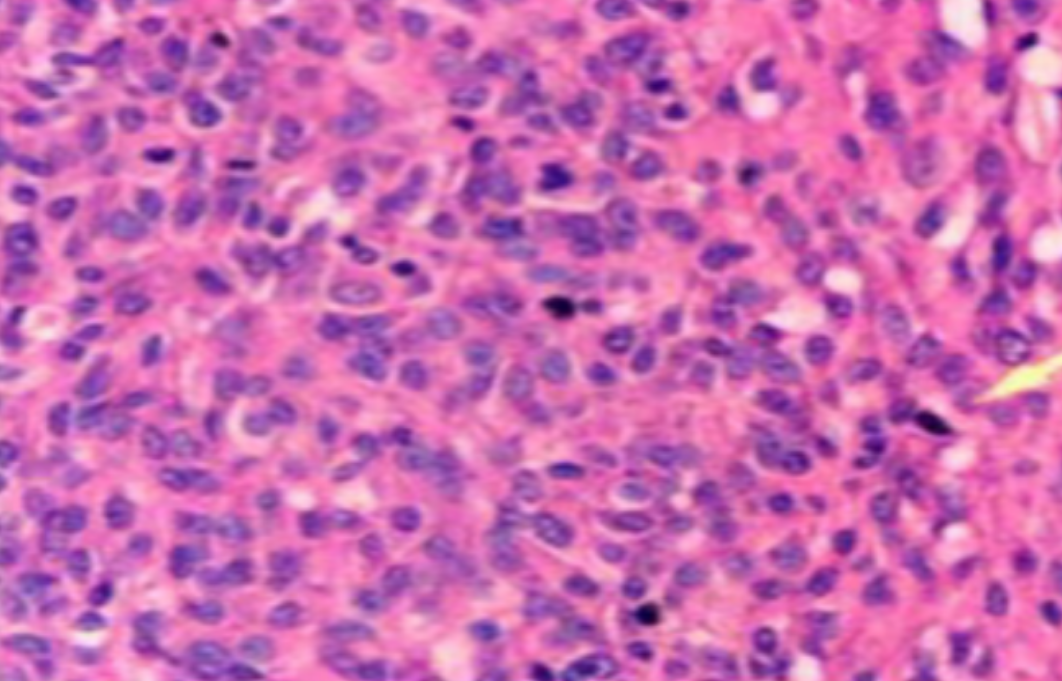

HE染色,全称苏木精-伊红染色法(Hematoxylin and Eosin staining),是最常见的组织切片染色技术之一,用于在显微镜下观察和分析组织或细胞的结构和形态。

虽然HE染色是最常见且最基础的染色技术之一,😭但在实验过程中,很容易出现各种情况导致染色切片质量参差不齐。所以,小编根据以往实验经验,给大家整理归纳出了15个HE染色中的常见问题,还包含问题原因分析以及解决方法哦~